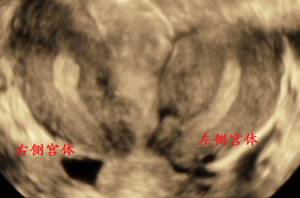

四、双子宫

超声可见两个宫体及其内膜腔回声,且双侧基本等大。纵切连续扫查,左右两宫体如两个分开的单角子宫一般,其内膜腔都向各自一侧延续。横切面显示两套环形肌层及其内膜腔回声,从宫颈管至宫底水平扫查,两宫体回声均逐渐增大,且相行渐远。

三维超声上,子宫形态呈两个单角子宫,各自偏向一侧,其内的宫腔形态均呈香蕉状,各自偏向一侧。